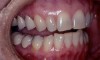

This patient wanted to know more about improving her smile (Figure 6). She had always felt like her smile never looked quite right after she had orthodontics as a teenager. A smile with better proportion, contours, and whiter color was her goal.

Figure 6  The full smile of case two.

Figure 6

Figure 7  The canine teeth were moved mesially into the space left by the congenitally missing lateral incisors.

Figure 7

Figure 8  Having the premolars in the position of the canine leaves inadequate contour to provide disclusion of the posterior teeth. Note how the incisal plane moves apically after passing the lateral position.

Figure 8

The origin of the patient’s esthetic concerns and functional issues proved to be the same: the patient was congenitally missing her lateral incisors. The solution for this esthetic deficit during her adolescent years was to move the canines into the position of the lateral incisors and then recontour (flatten the incisal edge) to make it look like a lateral. The premolars were then moved mesially into the canine position (Figure 7). The end result was a solution that closed an edentulous space, yet left a functional deficit. The premolars lacked the proper contour to allow immediate posterior disclusion in an excursive movement (Figure 8). After many years, this functional deficit led to the previously described signs of instability.